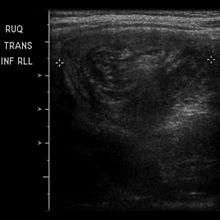

An intussusception is often suspected based on history and physical exam, including observation of Dance's sign. A digital rectal examination is particularly helpful in children, as part of the intussusceptum may be felt by the finger. A definite diagnosis often requires confirmation by diagnostic imaging modalities. Ultrasound is the imaging modality of choice for diagnosis and exclusion of intussusception, due to its high accuracy and lack of radiation. The appearance of target sign (also called "doughnut sign" on a sonograph, usually around 3 cm in diameter, confirms the diagnosis. The image seen on transverse sonography or computed tomography is that of a doughnut shape, created by the hyperechoic central core of bowel and mesentery surrounded by the hypoechoic outer edematous bowel.[7] In longitudinal imaging, intussusception resembles a sandwich.[7]